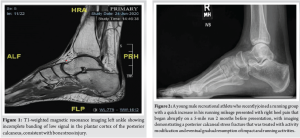

A 57-year-old female presented with instant left-sided heel pain after stepping off a step at home. Clinical examination revealed mild swelling over the medial side of the left heel upon inspection, with tenderness over the swelling on palpation, with no distal neurovascular deficit elicited. The patient’s past medical history included hypothyroidism, asthma, and chronic smoking. Investigations included plain radiographs of the left foot and ankle, with no obvious fractures visible. As a result, a magnetic resonance imaging (MRI) was obtained, which confirmed a stress fracture of the left os calcis (Fig. 1).

The calcaneus is one of seven tarsal bones and is part of the hindfoot, which includes the calcaneus and the talus [1]. Stress fractures are relatively uncommon injuries, accounting for approximately 1–7% of all athletic injuries, occurring as a result of overuse [2,3]. They occur over time as a result of repetitive forces causing microscopic damage to the bone, as well as in cases where physical activity is increased in the setting of relative energy deficiency [4]. The signs and symptoms of stress fractures may include: Slowly developing generalized pain in the heel area, swelling in the heel area, as well as a positive calcaneal compression test [4]. The diagnostic capability of X-rays is limited, as stress fractures may only appear on X-ray once the fracture has started to heal (after 2–3 weeks of symptoms), at which point a sclerotic or radiolucent line may be visible. With more advanced imaging, a stress fracture will appear darker on the bone scan than an uninjured area. With this type of injury, this would be visualized on MRI as a line in the trabecular calcaneus, hypo-intense in all sequences, surrounded by an area of abnormal bone marrow signal due to local edema (hypo-intense on T1-weighted and hyper-intense on fluid-sensitive images) [5-7] (Fig. 2-4).